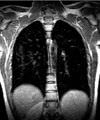

Последние исследования ученых показывают, что одной из причин развития рака легких являются вирусы.

При проведении исследований над пациентами, которые страдали от рака легких, выяснилось, что большой процент среди них переболели такими вирусами, как вирус папилломы, корь, стали причиной рака легких.